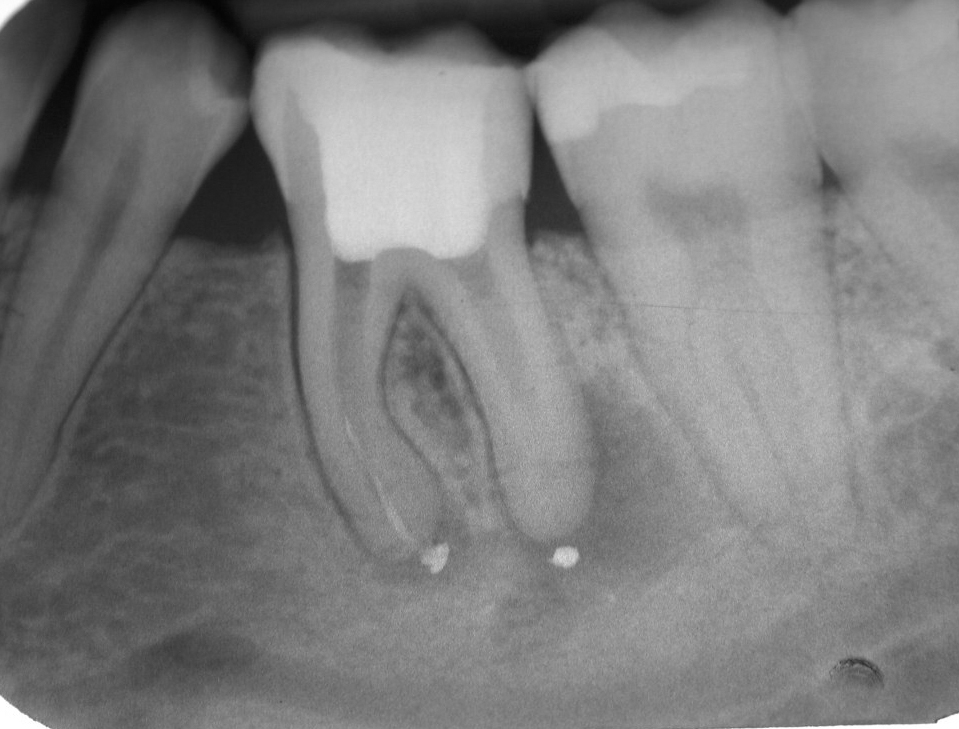

Fast 15 Jahre im Recall – Zahn 36 (2)